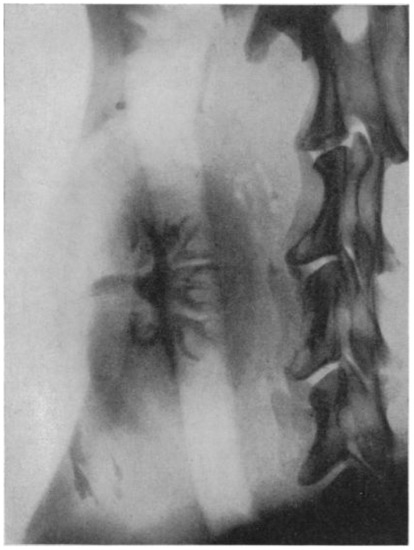

In the same year as the first human-to-human kidney transplantation (1933), the scientist Irène Joliot-Curie, daughter of Maria and Pierre Curie, showed that radioactive elements can be produced artificially. This was the essential step toward the discovery of Iodine-131 and Technetium-99m, the cornerstones of nuclear medicine [27,28]. Although the development of kidney transplantation stagnated during World War II, the innovation of X-ray imaging and radioactivity skyrocketed. Radiotracers became a serious factor in medical practice in the 1960s, the golden era for kidney transplantation innovations [29,30]. The medical fields of kidney transplantation and nuclear medicine crossed paths in the application of renal scintigraphy (renography). This technique was first performed using Iodine-131-Hippuran and later replaced by Technetium-99m mercaptoacetyltriglycine (MAG3) in 1988, due to better count statistics and a lower radiation dose [31,32]. In 1965, Figueroa and colleagues published their report on the use of Chlormerodrin (Hg-203) after kidney transplantation in The New England Journal of Medicine (Figure 2) [30]. With the use of radioactive Xenon (Xenon-133), intra-operative renal blood flow measurements were tested in 1967, injecting the radioactive substance directly into the renal artery, while recording the activity over the entire kidney allograft [33]. MAG3 renal scintigraphy is still used for post-transplantation evaluation, mainly for the diagnosis of vascular and urological complications [34].

Figure 2.

The result of a renal scintigraphy with Chlormerodrin (Hg-203), presented by Figueroa and colleagues in The New England Journal of Medicine. 1965. Left image: “Distinct shadow of the grafted kidney, eleven days after transplantation”; right image: “renal scan thirty-six days after transplantation. Note the great improvement in the renal contour. The shadow in the left lower quadrant is produced by the radioactive urine in the bladder” [30].